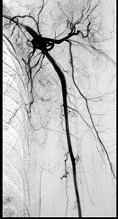

- 单项选择题43岁女性患者,突发左手疼痛伴多个指头麻木就诊, 行左上肢动脉照影,示左侧桡动脉广泛的充盈缺损, 结合临床考虑左侧桡动脉病变为 ( )

A、桡动脉夹层

B、桡动脉炎

C、桡动脉真性动脉瘤

D、桡动脉血栓形成

E、桡动脉假性动脉瘤